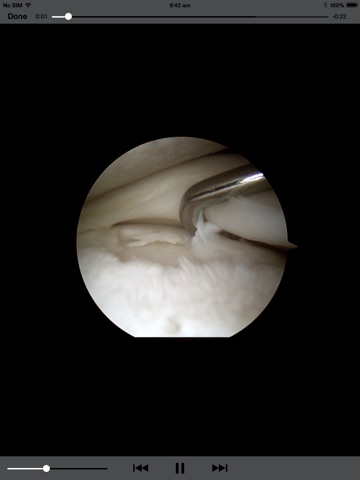

The Medic App is an app for surgeons who utilise Medicap Surgical documentation and recording system. Stream surgical images, video and reports directly to your own personal Apple device to browse or consult with your patients. Save content and take it away with you by simply saving the content to your iPad.

The Medic App is an effective tool for any surgeon or hospital staff member to transport and share content from our servers.